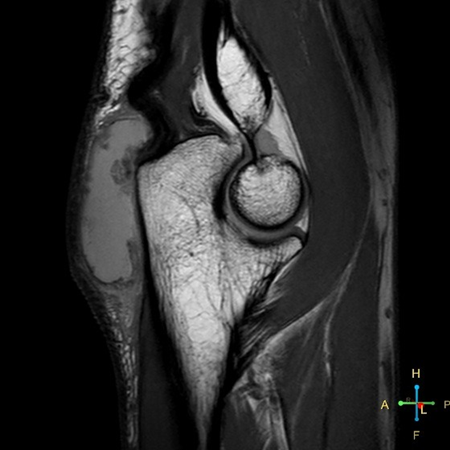

Sagittal PDw TSE